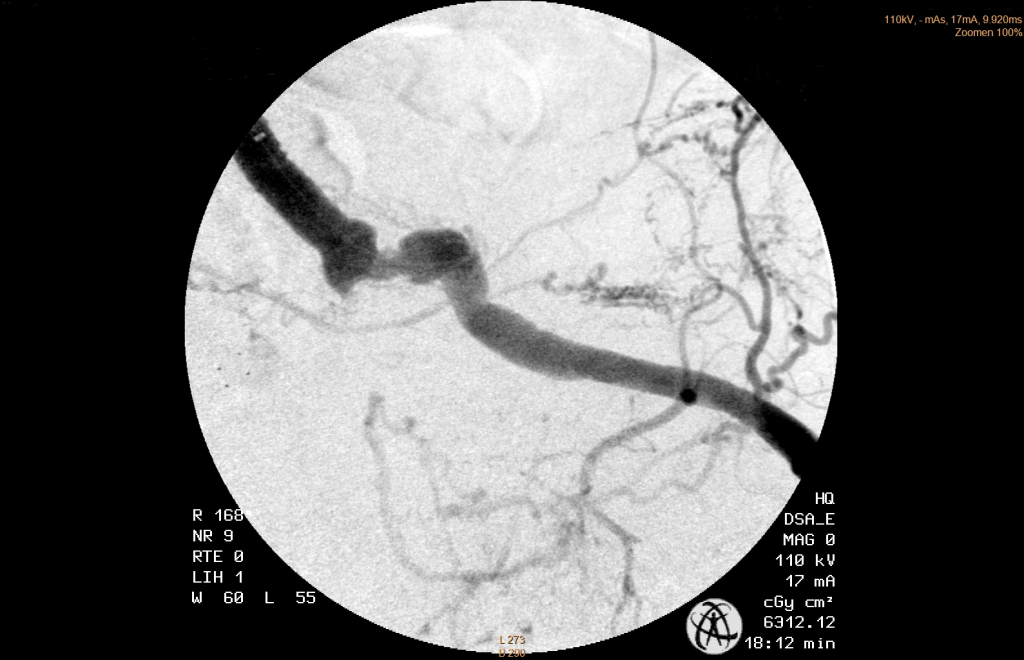

A left brachial access was established and a long sheath placed at the entry of the hypogastric artery. Afterwards it was easy to anchor the guidewire in the small deepening, enter and cross the leasion with the help of a support catheter. The correct intraluminal position past the leasion was confirmed. After pre-dilatation the leasion was stented with a 5mm BMS .